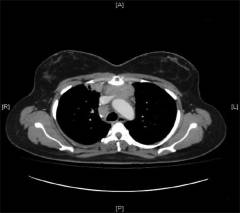

Обследование внутренних органов Проводят УЗИ, компьютерную, магнитно-резонансную томографию для того, чтобы оценить состояние селезенки и других внутренних органов, выявить их увеличение.

Исследования проводятся по назначению врача.

Рентгенография, компьютерная томография, магнитно-резонансная томография грудной клетки У многих больных выявляется увеличение тимуса и внутригрудных лимфатических узлов.